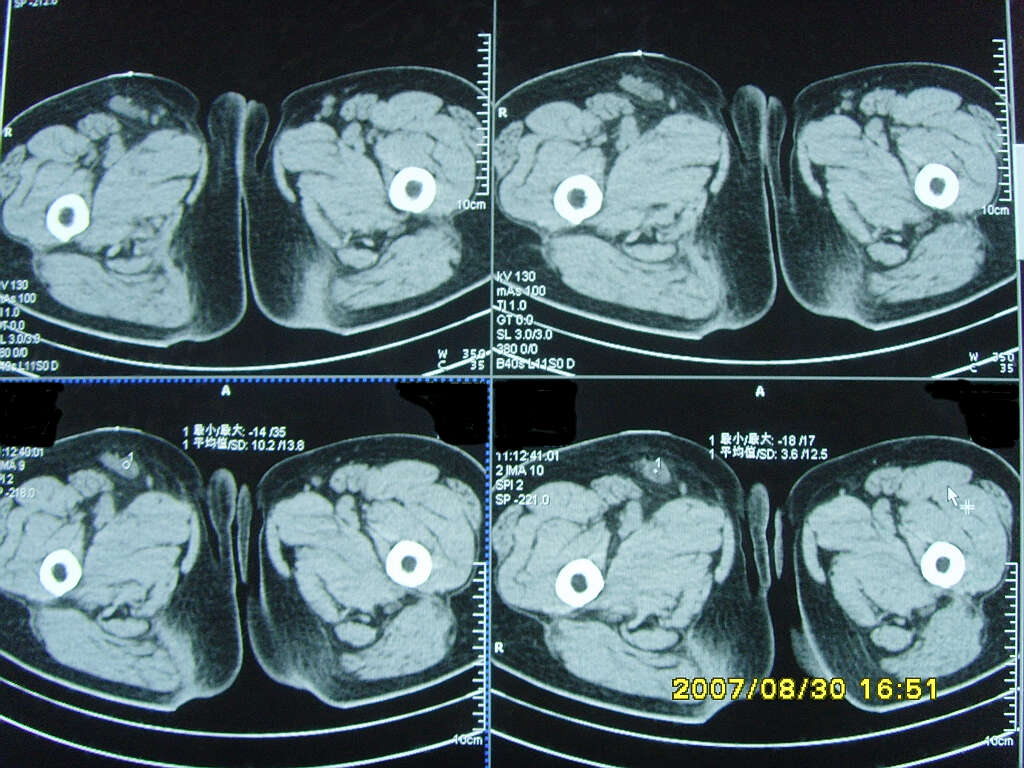

以下是引用zjzjr在2007-9-11 22:21:00的发言:[br]右侧股骨上段前部皮下可见不椭圆形软组织密度影,增强呈环形强化,周围皮下脂肪混浊,考虑感染性病变,不知临床症状如何.